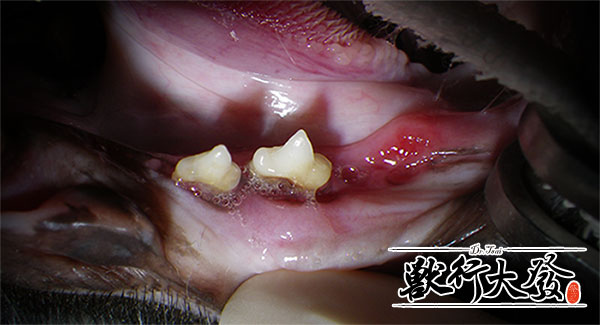

這是貓咪牙周病(periodontitis)

這是貓咪牙體吸收(tooth resorption, TR)

他們是不是看起來都一個樣!?

由此可知

沒有經過詳細檢查,我們怎麼知道是不是真正的口炎呢?